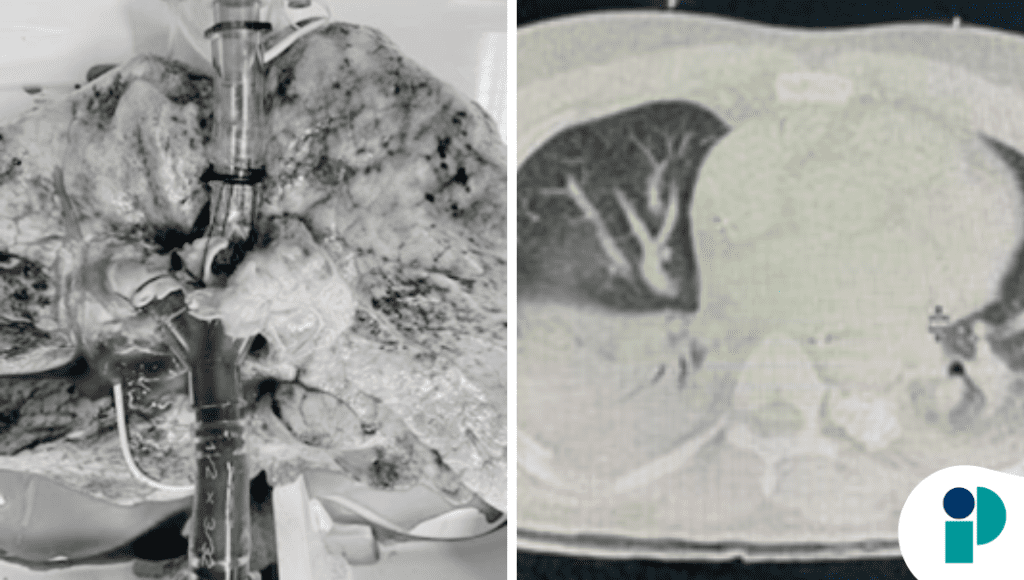

En trasplante pulmonar, los desafíos técnicos pueden surgir incluso en escenarios controlados como la perfusión pulmonar ex vivo (EVLP). En este caso, un equipo quirúrgico se enfrentó a un bloqueo segmentado del pulmón donante que complicó la perfusión pulmonar fuera del cuerpo, un paso crítico para evaluar la viabilidad del injerto antes de la implantación.

El reporte, centrado en un pulmón donante con hallazgos anatómicos atípicos, describe cómo la presencia de obstrucción vascular segmentaria generó discrepancias en la distribución del flujo durante la EVLP, lo que dificultó la valoración funcional estándar del pulmón. Este tipo de bloqueo, aunque infrecuente, puede impactar la decisión de proceder con el trasplante o ajustar la estrategia de manejo.

La EVLP se utiliza para mantener y evaluar pulmones donantes fuera del cuerpo del receptor, permitiendo medir parámetros como compliance, resistencia vascular y oxigenación antes de decidir la aceptación del órgano. En este caso, la distribución irregular del flujo de perfusión debido al bloqueo segmentado obligó al equipo a implementar ajustes técnicos para equilibrar la perfusión y evitar daño adicional.

Aunque los bloqueos segmentados pueden relacionarse con alteraciones anatómicas congénitas o cambios vasculares adquiridos, su presencia durante EVLP destaca la importancia de una evaluación detallada de la anatomía vascular pulmonar donante antes y durante la perfusión. El manejo exitoso de este caso sugiere que, con monitoreo cuidadoso y ajustes en tiempo real, es posible sobrepasar estas dificultades técnicas y confirmar la viabilidad del injerto.

Este caso pone de relieve que los procedimientos avanzados como la EVLP deben considerar no solo parámetros fisiológicos globales, sino también variaciones anatómicas individuales que pueden afectar la eficiencia de la perfusión y, por ende, las decisiones de trasplante.